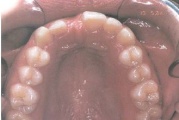

ülemine hambakaar on alumisest laiem nõnda palju, et hambad kokku ei puutu